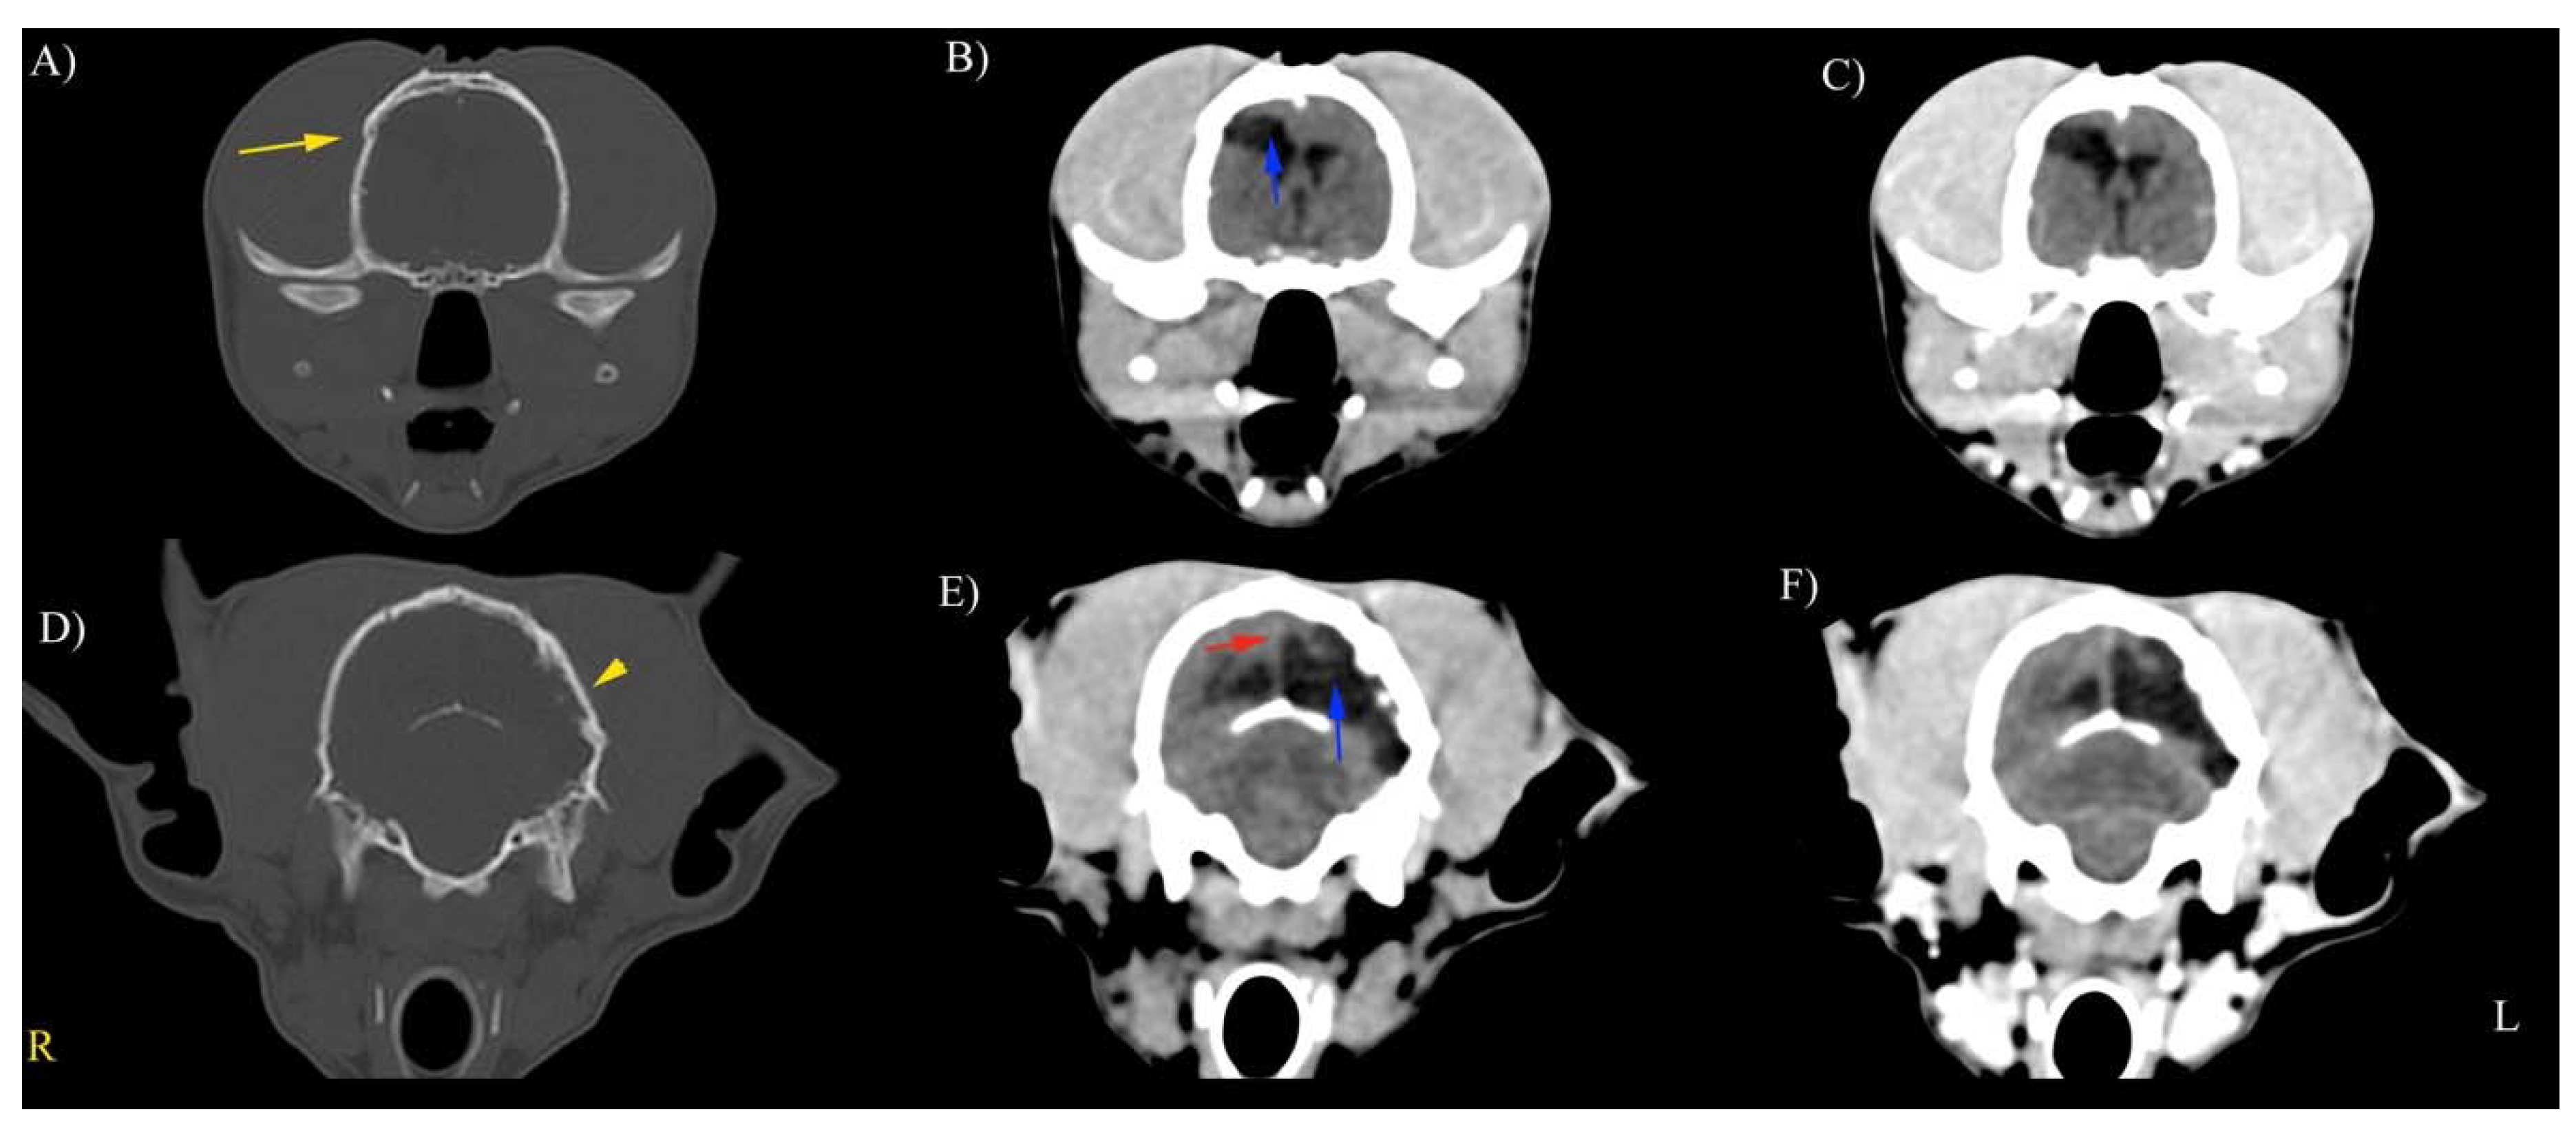

3.3. CT Findings

|---|---|---|---|

| Cranial vault fractures (depression) | 3 (50%) | 1 (17%) | 2 (33%) |

| Abnormalities of the parenchyma | |||

| Mild | Moderate | Severe | |

| Cerebral hemisphere or cerebellum as a single lesion | 3 (50%) | 2 (33%) | 1 (17%) |

| Multiple lesions | 2 (33%) | 3 (50%) | 0 |

| Intracranial hemorrhage | |||

| Intra-axial | 3 (50%) | 3 (50%) | 0 |

| Extra-axial | 2 (33%) | 1 (17%) | 1 (17%) |

| Other findings | |||

| Midline shift | 2 (33%) | 1 (17%) | 0 |

| Lateral ventricle asymmetry | 2 (33%) | 1 (17%) | 2 (33%) |

| Hydrocephalus | 1 (33%) | 1 (17%) | 2 (33%) |